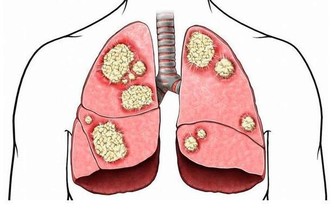

肝臟能解毒,並非"百毒不侵"

肝臟是身體內以代謝功能為主的一個器官,可以處理一些化合物,不讓毒素入侵機體。

但是肝臟的解毒作用是有一定限度的,並非“百毒不侵”,

毒物過多或肝臟受損,解毒功能發生障礙,仍然會出現中毒現象。